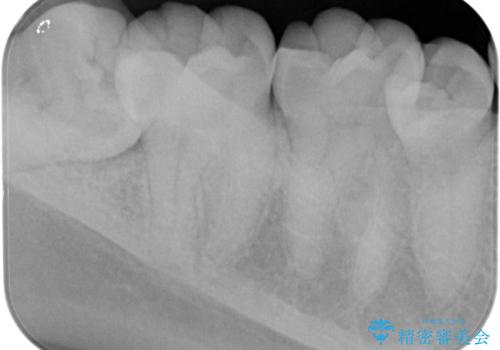

先に虫歯を徹底的に取り除き親知らずを抜歯してe-maxインレーで治療を行いました。

適合の良い詰め物が入りました。

親知らずは虫歯になるリスクが高いため抜歯をする事をお勧めします。